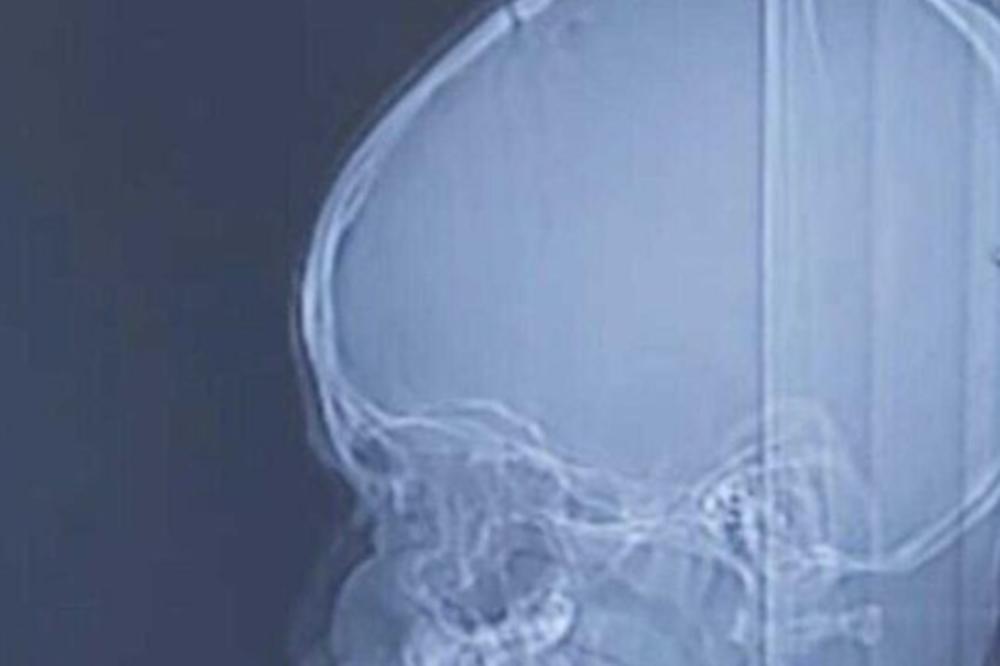

Živi crv dugačak nešto manje od 13 centimetara izvađen je iz mozga jednog 23-godišnjeg Kineza posle 17 godina.

Posle skenera, lekari su pronašli uvijenog parazita u mozgu pacijenta, a Čenu je dijagnostifikovana sparganosis mansoni, retka parazitska bolest.

Čen se sada polako i uspešno oporavlja nakon što su lekari izvadili crva iz njegovo mozga koji je bio dugačak nešto manje od 13 centimetara, a za koga se procenjuje da je parazitirao oko 17 godina.